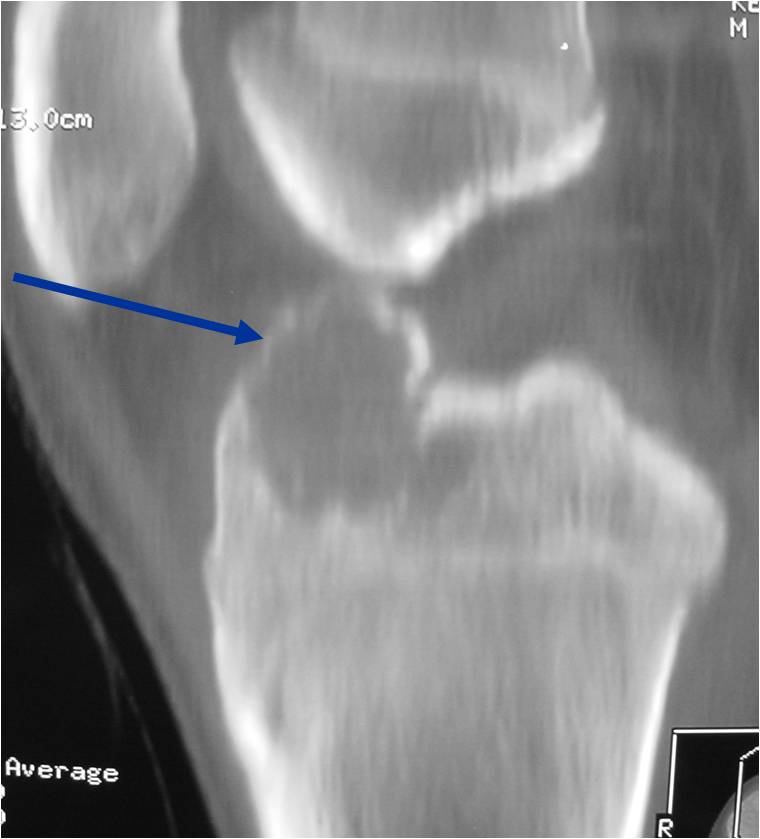

General Information Enchondroma is a benign indolent intramedullary hyaline cartilage neoplasm Accounts for 10% of all benign osseous tumors Limited growth, most lesions are less than 5 cm in maximal dimension Bones grow from a cartilaginous growth plate that...